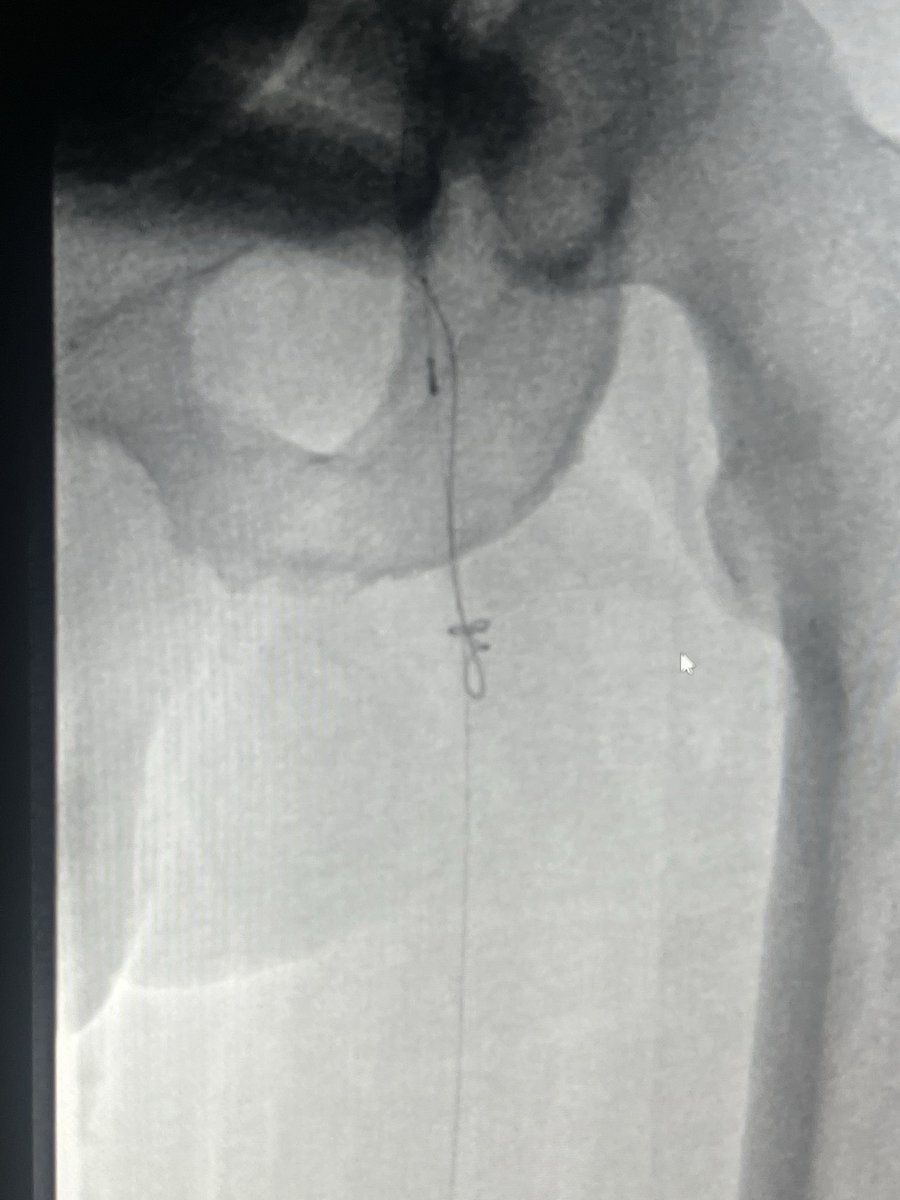

@SriniTummala @SIRRFS @JayMathewsMD @AmputationSuck @_backtable Here’s the fix in action. Punctured the patent CFA, directed the needle about ~2 cm into the occluded SFA , sent V18 down over a CXI. Externalized through the pedal sheath. Therapy from the original retro sheath/access. Luminal crossing on IVUS. All in all about 90 minutes.